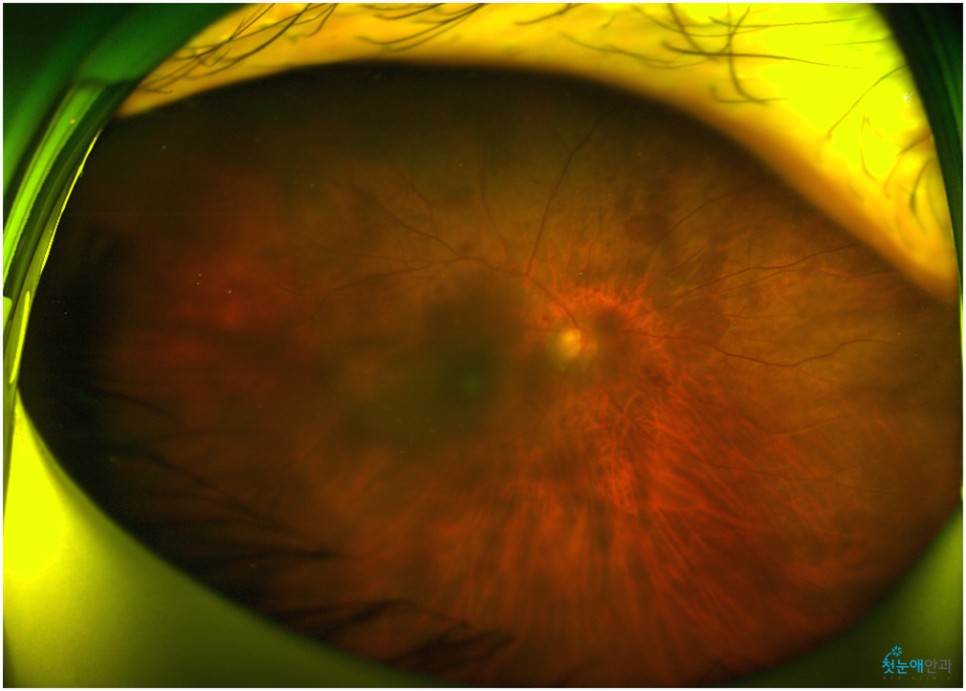

백내장이 상당히 진행되면 수정체가 흐려져 눈 아래의 망막 관찰이 어렵습니다.때문에 사진을 찍어 검사해봐야 하는데 위와 같이 흐릿한 사진이 찍혀 사실상 망막 관찰이 어렵습니다.뿐만 아니라 심한 백내장은 부분마취 수술 진행이 어려워 안구마취나 전신마취로 수술하거나 종합병원으로 전환해 수술해야 합니다.뿌옇게 변했는데도 그냥 놔두면 위 사진처럼 더 심해져 시력이 저하되는 상황까지 이어지게 됩니다.

모든 수술이 종료된 후 시력 검사도 다시 실시했습니다.수술 이전에는 우안 0.05 좌안 0.1이었던 시력으로 전 세계가 흐릿해 보였지만 백내장 인공수정체 수술을 알게 된 후 0.8로 호전돼 일상생활을 하는 데 불편함도 개선했습니다.